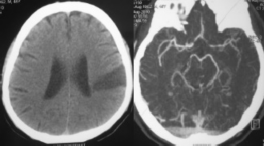

Hình 3.10. Nhồi máu não vùng ranh giới sau, ranh giới tưới máu giữa động mạch não giữa và não sau. Trường hợp này tắc động mạch cảnh trong trái ngoài sọ, nhưng bàng hệ đã đủ lấp một phần đoạn cuối của động mạch này